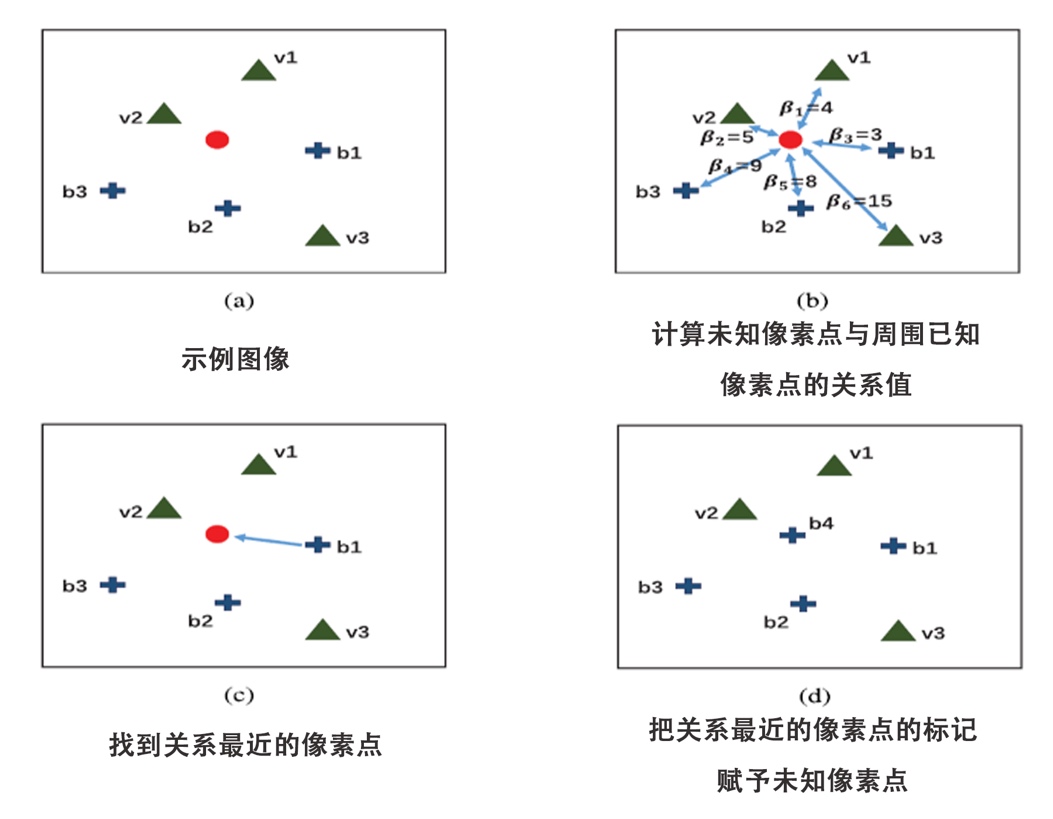

图三 分层抠图模型的算法框架和实例展示 图四和图五分别展示了分层抠图模型算法中两个步骤的基本流程,其中绿色代表血管点,红色代表未知点,蓝色代表背景点。在第一步对未知像素点的分层过程中,我们计算每个未知像素点与最近血管点的距离,并按该距离将未知点分层。在第二步分层更新过程中,从第一层开始,我们计算该层每个未知像素点和它最近的已知点(血管点和背景点)的关系值,选择每个未知像素点关系最近的已知点,把这个已知点的标记赋给未知的像素点。当该层所有的未知像素点更新后,我们再用它们继续对下一层的未知像素点进行更新,以此循环,直到最后一层更新完毕。

图四 未知像素点的分层示例流程图

图五 分层更新的示例流程图 本文通过与多个血管分割算法进行比较验证了所提算法的有效性,对比结果如图六所示。实验结果表明,基于分层抠图模型的血管分割算法在两个公开的数据库: DRIVE和STARE上均取得了较好的分割结果。下面我们给出一些血管分割的实例对比结果(如图七所示)。在图七的(a)(b)(c)(d)中,左图均为医生分割的结果,右图为基于算法所分割出的结果。不难看出,基于该算法所得到的分割结果,相比医生分割的结果,提取了更多复杂的特征信息。